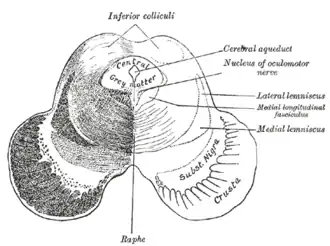

Transverse section of mid-brain at level of inferior colliculi.

Transverse section of mid-brain at level of inferior colliculi. -